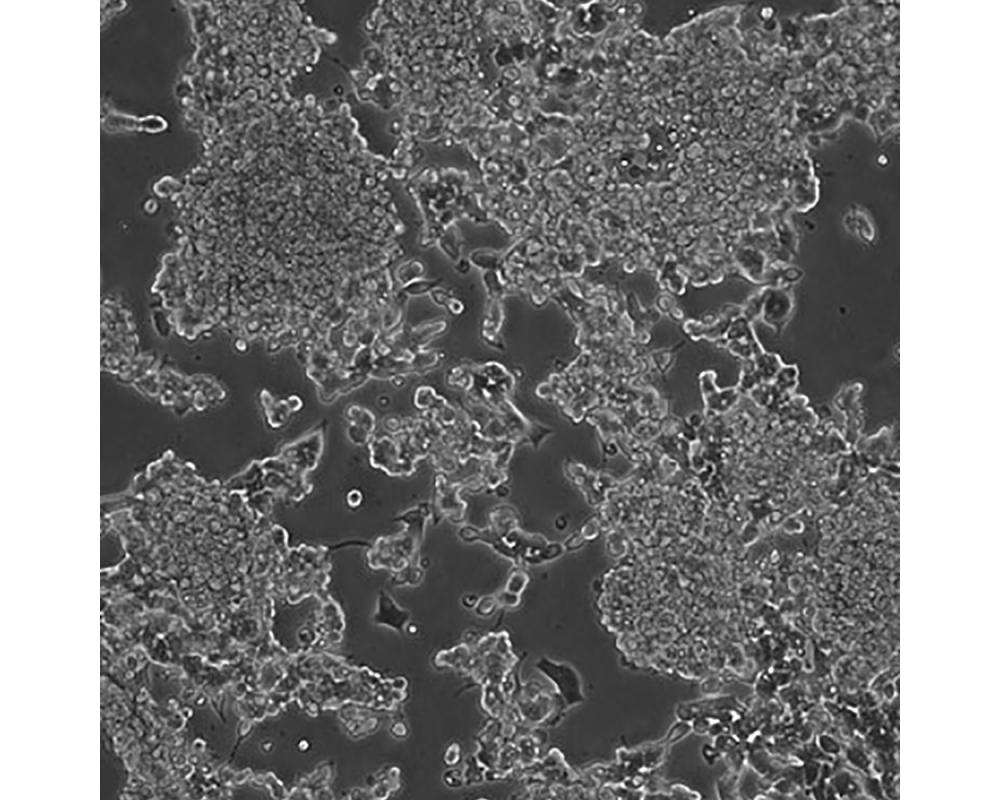

alpha TC1 clone 6

產品名稱 alpha TC1 clone 6

中文名稱 小鼠胰島素瘤胰島a細胞

組織來源 胰島素瘤;a細胞;C57BL/6xDBA/2

細胞種屬 小鼠

生長特性 貼壁

培養基 H-DMEM,90%;FBS,10%;雙抗。

傳代方法 1:2-1:4

培養條件 Atmosphere: Air, 95%; CO2, 5%。Temperature: 37℃